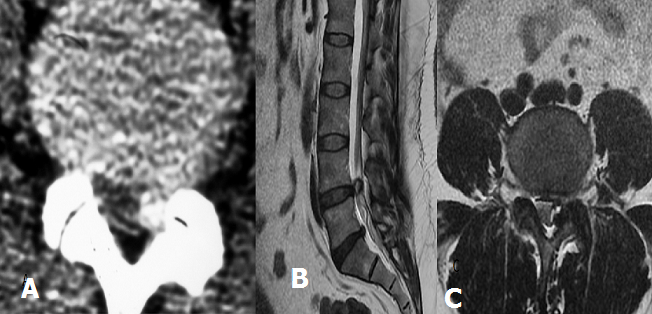

Le kyste synovial lombaire est une formation kystique para articulaire développée à partir de l’articulation interapophysaire postérieure et représente une étiologie rare non discale de lombalgies et/ou de sciatiques d'origine rachidienne. Nous rapportons le cas d'une femme de 50 ans qui consultait pour une radiculopathie L5 gauche. La TDM lombaire (A) montre au niveau de L4-L5 une lésion arrondie de 15mm de diamètre, bien limitée présentant une paroi dense en regard de l’articulaire postérieure dégénérative gauche. L’IRM lombosacrée (B et C) mis en évidence un kyste synovial L4-L5 postéro-latéral gauche. La résection du kyste effectuée en bloc, est associée à une foraminotomie. L’évolution clinique est favorable. Le kyste synovial atteint le plus souvent le sujet d’âge moyen. La localisation est dans la majorité des cas lombaire plus volontiers à l’étage L4-L5. L’IRM est l’examen de choix dans le diagnostic des kystes synoviaux en montrant le siège du kyste, sa communication avec l’articulaire postérieure et son signal qui est variable en fonction de son contenu : liquidien identique au LCS, soit épais intense T1 et T2 ou à contenu gazeux (signal void area). Le traitement est avant tout médical, et repose sur l'injection intra-articulaire de corticoïdes au cours de l'arthrographie ou sous scanner. La chirurgie n'est indiquée qu'en cas d'échec du traitement médical.